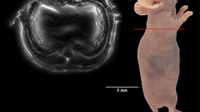

MRI machines typically acquire a variety of images of the same body part, each designed to create a contrast between different types of tissue. By comparing multiple images of the same region, radiologists can detect subtle abnormalities such as a developing tumor. But taking multiple scans of the same region in this way is time-consuming, meaning patients must spend long periods inside the machine.

The MIT algorithm dramatically speeds up this process. The algorithm uses information gained from the first contrast scan to help it produce the subsequent images. In this way, the scanner does not have to start from scratch each time it produces a different image from the raw data, but already has a basic outline to work from, considerably shortening the time it takes to acquire each later scan.

The software looks for features that are common to all the different scans, such as the basic anatomical structure. In particular, the algorithm uses the first scan to predict the likely position of the boundaries between different types of tissue in the subsequent contrast scans. Given the data from one contrast, it gives a certain likelihood that a particular edge will be in the same place. The result is an MRI scan that is three times quicker to complete, cutting the time patients spend in the machine from 45 to 15 minutes.